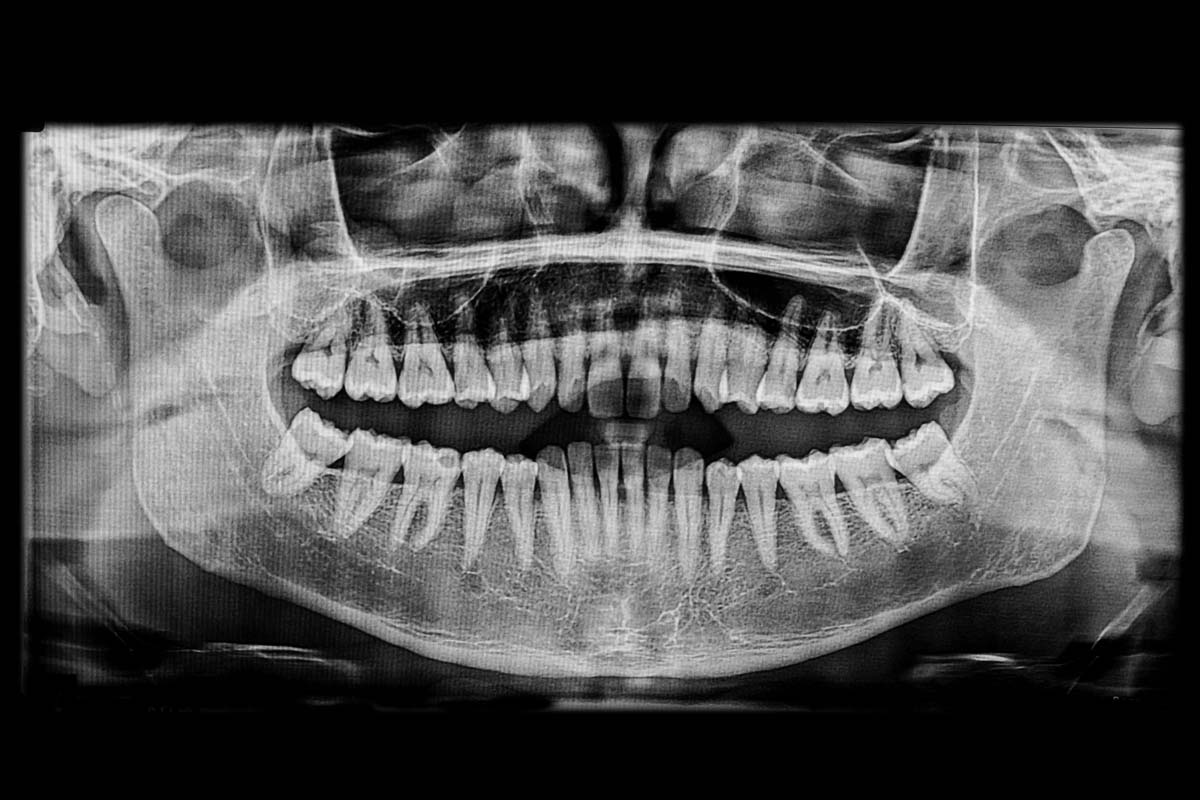

Auflagerungsplastik/Augmentation als Alternative zur Nervlateralisation zum Knochenaufbau im Unterkiefer

Auflagerungsplastik bedeutet, dass an einer anderen Stelle des eigenen Körpers eine Knochenscheibe entnommen wird, die dann auf den zurück gegangenen eigenen Knochen im Bereich des Knochenfortsatzes aufgelagert wird. Die Fixation erfolgt durch feine Mikroschrauben oder aber mit Implantaten selbst.

Der Knochen für diese Auflagerungsplastik kann an verschiedenen Entnahmestellen gewonnen werden, so z. B. am Beckenkamm, am Schienbein oder auch am Schädelknochen. Der Beckenkamm hat sich als die am häufigsten genutzte Entnahmestelle, insbesondere für größere Knochenstücke, durchgesetzt. Über einen Zugang im Bereich des Hüftknochens kann dann über einen ca. 2 cm langen Schnitt ein ausreichendes Knochenstück entnommen werden. Dieses wird anschließend nach entsprechender Präparation und Bearbeitung als sog. mono- oder bikortikales Transplantat auf den Knochen aufgebracht.

Wichtig ist es hierbei, auf eine ausreichende Knochenanlagerungsfläche zu achten. Auch der ortständige Knochen muss angefrischt werden, um ein Verwachsen mit dem neuen Knochen zu ermöglichen. Danach können die Implantate eingebracht werden.